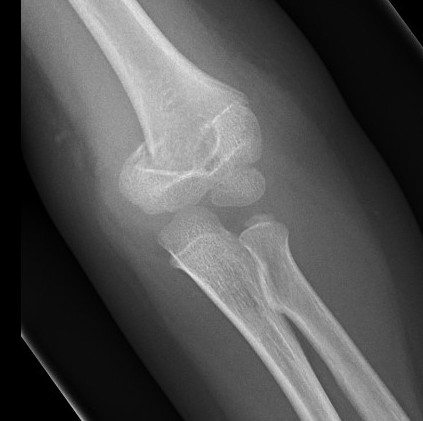

AP X-ray

Baumann's Angle

Technique

- angle between longitudinal axis humerus and capitellar physis

- should equal uninjured side

- 75o normal

Cubitus varus

- varus malposition > 81°

Cubitus valgus

- < 70o